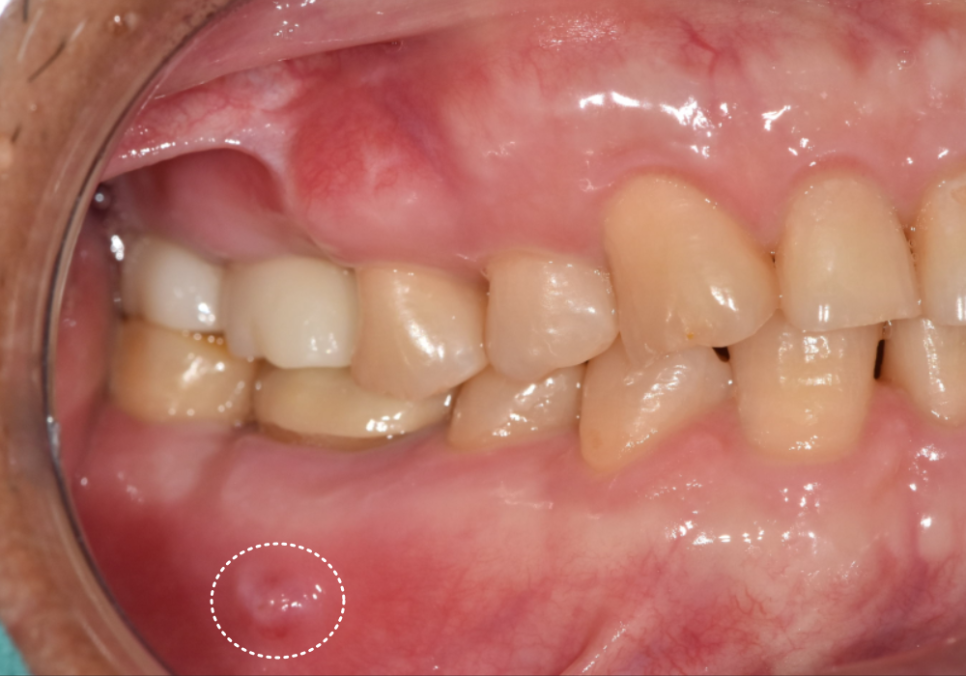

얼마 전 오른쪽 아래 어금니에

여드름 같은 게 생겼다며

저희 치과를 찾으신 환자분의 사례예요.

입안을 살펴보니 잇몸 겉에

뽈록한 고름 주머니가 보였는데,

환자분께서는 아프지도 않고 금방 가라앉길래

치료를 계속 미뤄오셨다고 해요.

하지만 잇몸 겉에 증상이 나타났다는 건,

잇몸 뼈는 훨씬 깊은 곳에서부터

녹고 있다는 뜻입니다.